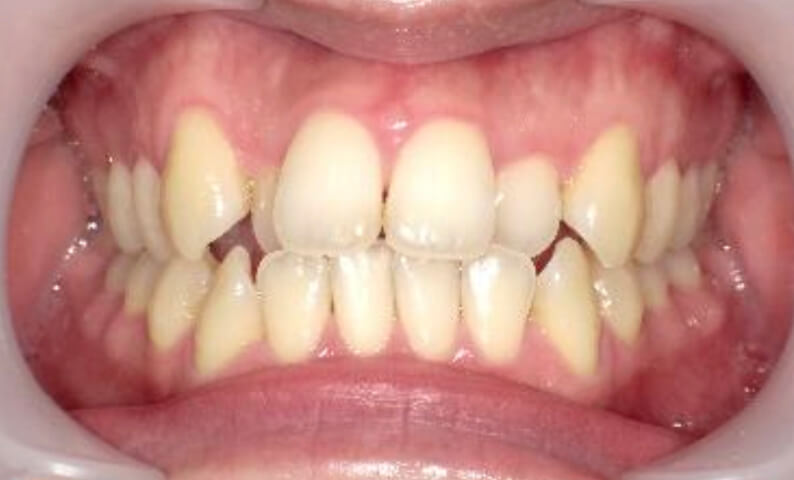

症例_024 上顎だけの部分矯正

治療期間:7ヶ月金額:30万円+税女性前歯のガタガタ上の前歯だけ

| Before | After |

|---|---|

|